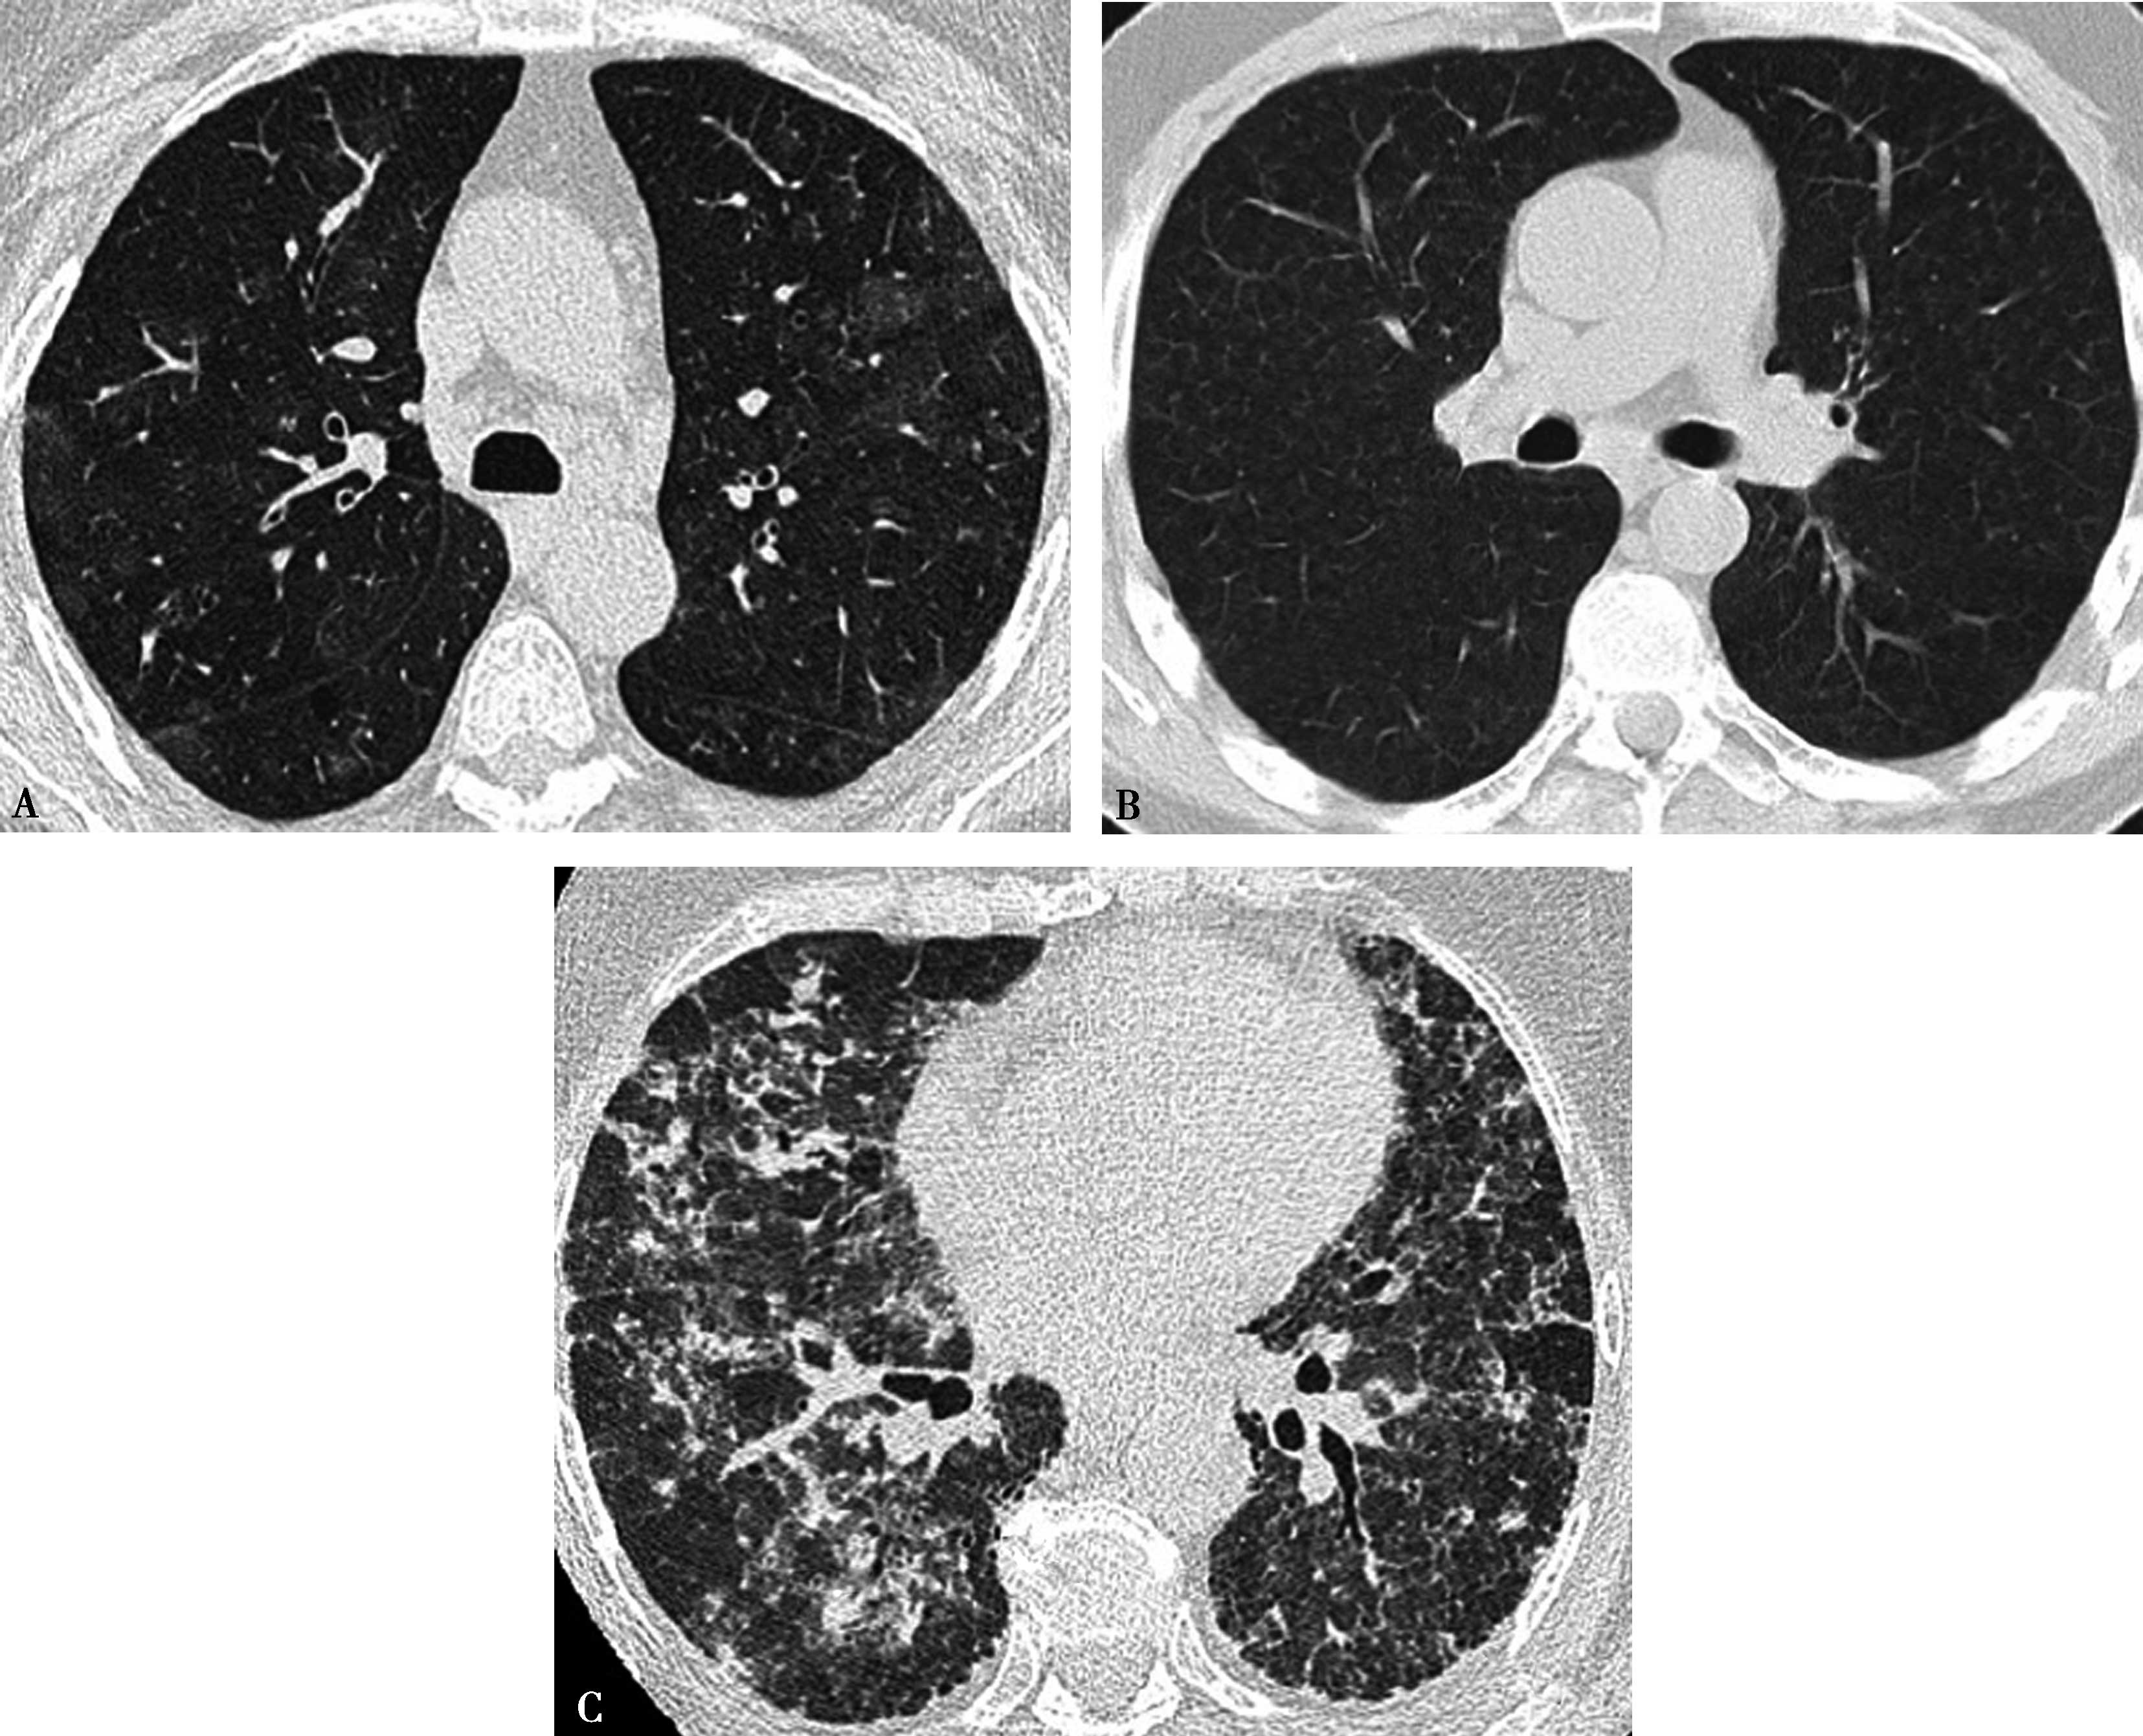

图8-3-2 正常肺组织

A.双能CT肺灌注成像(DELPI);B.核素 99m Tc-MAA SPECT/CT

图8-3-3 男,73岁,右肺下叶肺栓塞

A.双能CT肺灌注成像(DELPI);B.核素 99m Tc-MAA SPECT/CT。CT灌注扫描与核素检查结果一致

图8-3-4 男,69岁,双肺多发、急性肺栓塞

A.双能CT肺灌注成像(DELPI);B.核素 99m Tc-MAA SPECT/CT,CT灌注扫描与核素检查结果一致

图8-3-5 肺栓塞双能CT肺灌注成像(DELPI)

CTPA显示左肺舌叶段-亚分段、下叶内前基底段-亚分段未显影(A↑),灌注扫描示相应肺段灌注缺损(B↑),明确左肺舌叶段-亚分段、下叶内前基底段-亚分段肺栓塞诊断

图8-3-6 肺栓塞双能量CT能谱成像

A.右肺下叶外基底段栓塞(↑);B.能谱成像得到肺碘基物质图,梗阻肺段呈低灌注,清楚反映栓塞分布、程度(↑)